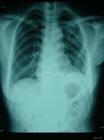

(一)中央型較周圍型多見,以原發性為多。原發性者,腫瘤發生於乾骺端髓腔內,呈一大的單房或多房狀透亮區,邊緣不規則,其間夾雜不規則的鈣化點和碎骨片。有時可見大量的絮狀鈣化及骨化斑塊遮蓋骨質區,形成一緻密的陰影。腫瘤膨脹生長,可使骨皮質變薄,一旦腫瘤穿破骨皮質或並發病理骨折、腫瘤很快侵入周圍軟組織中,形成軟組織腫塊,其內可見散在鈣化點。由於腫瘤的刺激,骨膜下常有多層狀新生骨形成,使骨皮質增厚或腫瘤穿破新生骨而出現“袖口”征。繼發性腫瘤的X線表現為:腫瘤的溶骨性透亮陰影增大,邊緣模糊,鈣化點增多,聚集成堆可見鈣化影溶解消失,最後腫瘤穿破皮質,在軟組織中發展並形成鈣化陰影。中央型軟骨肉瘤的重要表現為體積大的厚壁透亮區,區內有小梁形成和中央多葉性的髓腔內骨破壞。區內有許多散在的不規則的點狀、圈狀或片狀鈣化灶,常被描述成“棉絮樣”、“麵包屑樣”或“爆玉米花樣”。至後期,方有骨皮質的破壞,腫瘤穿透的骨皮質變模糊。軟組織內有腫瘤浸潤,但不一定有密度增加的鈣化陰影。骨膜反應較少。骨內膜側的骨皮質常呈貝殼狀凹陷,這是由於腫瘤的小葉狀輪廓造成。病理性骨折可使腫瘤迅速穿入軟組織,在骨外腫塊內出現鈣化的緻密陰影。(二)周圍型軟中央型少見。其中繼發性較原發性為多。骨軟骨瘤的惡性變,常在原發骨軟骨瘤的基礎上顯示軟骨帽增大變厚,形成界限模糊的軟骨組織腫塊,腫瘤內及其周圍軟組織中,有多量散在的斑點狀或絮狀不規則鈣化,有時可有粗而長的新骨形成,骨質部份也可顯示小梁紊亂和破壞徵象。軟骨瘤惡變除顯示生長迅速外並也可由於腫瘤的破壞而使原有之典型軟骨瘤表現消失。少數病例可發生袖口狀骨膜反應。外圍型軟骨肉瘤顯示病損旁的軟組織內有很淡的、鈣化很少的陰影,並有和表面垂直的放射狀骨刺,它們的外側面變為扁平,這是和骨肉瘤的放射狀骨刺的鑑別點。髓腔一般不受累,骨皮質也很少被侵犯,但在早期病例可見骨外膜被掀起,呈唇樣,亦可出現Codman三角。